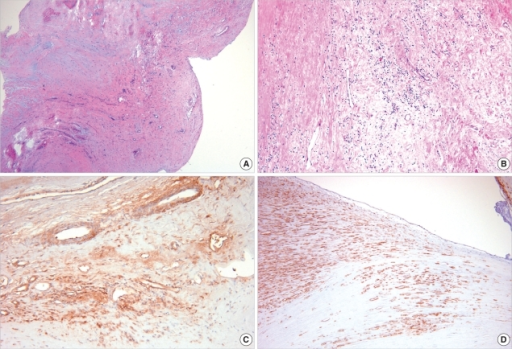

Histology classically shows reactive histiocytes with slender, wavy nuclei are known as Anitschkow cells, Aschoff bodies, gigantic cells, and fibrinoid material.

Chronic rheumatic heart disease develops when rheumatic fever-related valve scarring leads to stenosis with the classic fish-mouth appearance.

In chronic rheumatic heart disease, the chordae tendineae and cusps thicken as a result of the mitral valve being involved almost always.

Quite often the aortic valve is involved, which results in the commissures fusing together.

Other valves are less commonly involved and complications include infectious endocarditis.